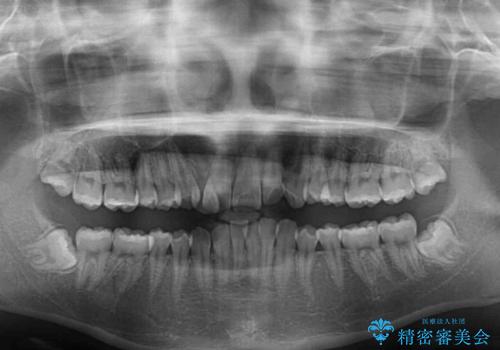

- 八重歯やデコボコをインビザラインで治療したいとのことで来院された患者様です。

インビザライン単体で治療を行うには叢生が強いと判断されたため、事前にワイヤー装置で抜歯矯正を行い、ある程度改善してからインビザラインにて仕上げていくこととしました。

- 症状により、抜歯が必要な場合があります